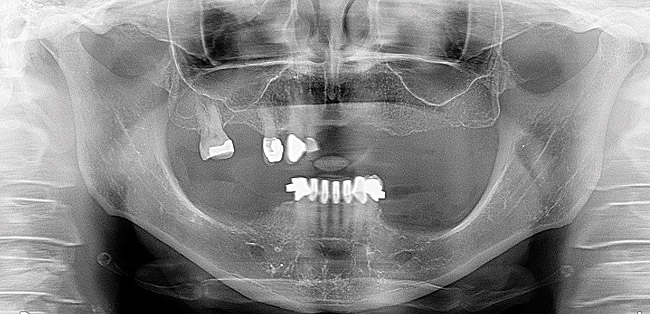

Figure 2  Preoperative panoramic radiograph showing the existing dentition.

Figure 2

A 63-year-old woman presented with upper and lower partial dentures (Figure 1). She had become frustrated with the lack of stability of the partials and the failing abutment restorations. She was also concerned about her appearance. The patient’s present health condition was documented, which included arthritis, chronic lower back pain, chronic narcotic use, and hepatitis. The patient was presently on a regimen of Celebrex, Fiorcet, and oxycodone. It was also noted that the patient had an allergy to codeine.

After a clinical examination was performed including diagnostic digital radiographs (Figure 2), diagnostic study models, photographs, and a CBCT scan, treatment options were discussed and the patient’s future expectations were addressed and documented. She had received a previous treatment plan and had been told she needed a sinus lift and a bone augmentation but decided against them. Her desire was to have a fixed solution so she would not have to remove her denture teeth.